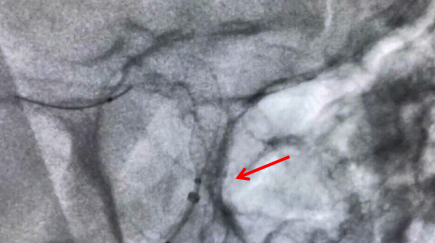

近日,我院神經(jīng)外科成功實(shí)施重慶市第二例、璧山區(qū)首例Surpass Evolve血流導(dǎo)向密網(wǎng)支架介入手術(shù),標(biāo)志著我院顱內(nèi)動(dòng)脈瘤治療技術(shù)實(shí)現(xiàn)新突破,也代表我院神經(jīng)外科介入技術(shù)再上新臺(tái)階。

48歲的袁先生兩周前因發(fā)作性口角歪斜前往我院治療,期間行DSA造影檢查顯示其右側(cè)頸內(nèi)動(dòng)脈眼段多發(fā)動(dòng)脈瘤形成,呈串珠樣、不規(guī)則分葉狀,隨時(shí)可能破裂,危及生命,風(fēng)險(xiǎn)極大。考慮到患者年紀(jì)輕,動(dòng)脈瘤為多發(fā),累及血管較長,為達(dá)到良好的治療效果,保證其術(shù)后更高的生活質(zhì)量,我院副院長、神經(jīng)外科專家牟科杰主任醫(yī)師,神經(jīng)外科副主任(主持工作)徐忠燁主任醫(yī)師,副主任薛軍副主任醫(yī)師經(jīng)全面細(xì)致討論研究,最終決定應(yīng)用血管內(nèi)血流導(dǎo)向裝置(密網(wǎng)支架)植入技術(shù)隔離其多發(fā)動(dòng)脈瘤,重建患者受累及的顱內(nèi)動(dòng)脈。

牟科杰主任醫(yī)師介紹,顱內(nèi)動(dòng)脈瘤是血管壁形成的囊狀突起,是顱內(nèi)“不定時(shí)炸彈”,動(dòng)脈瘤介入治療,已經(jīng)從彈簧圈栓塞時(shí)代進(jìn)展到了血流導(dǎo)向密網(wǎng)支架治療的時(shí)代。傳統(tǒng)的治療方法是單純彈簧圈栓塞或支架輔助彈簧圈栓塞或開顱夾閉,但對(duì)于一些瘤頸寬、瘤體大、多發(fā)動(dòng)脈瘤的患者,血流導(dǎo)向裝置成為一種最佳的治療手段。通過血流導(dǎo)向密網(wǎng)支架的釋放,重建血管內(nèi)血流方向,使動(dòng)脈瘤血栓化,促進(jìn)血管內(nèi)皮的再生及修復(fù),最終使瘤頸閉合而治愈。血管重建技術(shù)是顱內(nèi)動(dòng)脈瘤血管內(nèi)治療的重大突破,它使得一些復(fù)雜的腦動(dòng)脈瘤治療風(fēng)險(xiǎn)相對(duì)降低,術(shù)后復(fù)發(fā)率低,同時(shí)也讓手術(shù)時(shí)間大為縮短,為復(fù)雜動(dòng)脈瘤的治療帶來了全新方法。4月19日上午,手術(shù)歷時(shí)兩小時(shí)順利完成。

手術(shù)中釋放支架圖片